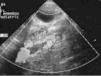

Se realizan las siguientes pruebas complementarias: radiografía de tórax donde se observa discreta cardiomegalia y signos de edema agudo de pulmón; ecografía abdominal (fig. 1) objetivándose un gran trombo que ocupa prácticamente toda la luz de la aorta abdominal desde la parte distal de la mesentérica superior hasta la bifurcación de ambas ilíacas. Ecografía transfontanelar: presencia de un trombo en el seno longitudinal superior, confirmado en la resonancia magnética (fig. 2) y en la angiografía cerebral (fig. 3) realizadas posteriormente.

Figura 2. Resonancia magnética donde se observa un trombo en el seno longitudinal superior.

Figura 3. Angiografía cerebral donde se confirma la presencia de un trombo que ocluye parcialmente el seno longitudinal superior.